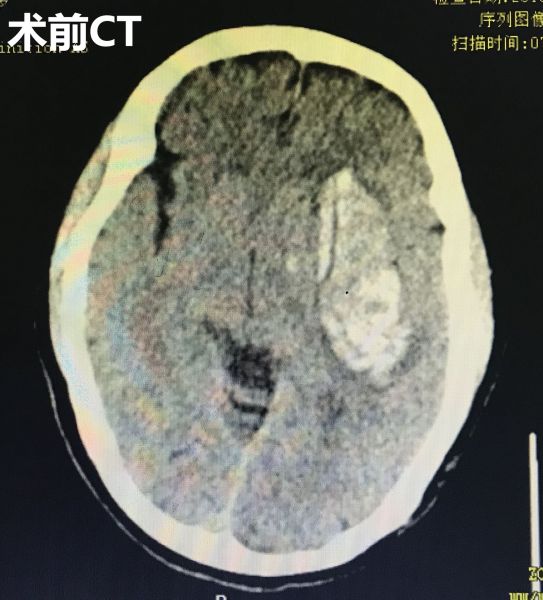

12月10日清晨,神经外科二病区一位脑出血病患的陪护家属突发意识不清倒在病房内。值班医护人员迅速启动卒中绿色通道,马上安置病人并完善相关检查。CT提示该患者为急性左侧基底节区脑出血并血肿形成,且血肿量大有急诊手术指征。但家属告知患者既往长期服用“阿司匹林”抗血小板聚集治疗,这将大大增加手术的风险。做手术可能会出问题,不做手术病人则可能死亡,怎么办?这确实让人左右为难。

术前CT影像